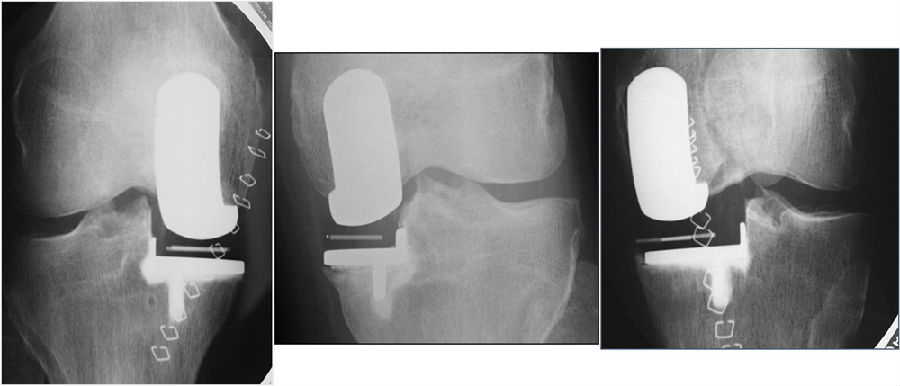

假体组件的位置:内外侧

股骨钻孔方法:插入髓内杆,插入导向器并设置为G型夹所选厚度,插入连接器以确保10°屈曲,保证6mm孔(股骨柱)在股骨髁正中间,避免前内侧悬出,注意导向器的外侧移动。钻孔的位置直接决定假体的位置。

可以通过解剖定位法确定这两个孔的位置,即是在股骨内髁的中线上用电刀画线,两个孔刚好在这条线上为合适,注意画中线的时候要现将内侧髁间窝骨赘去除,此时线才是准确的。另外还可以通过胫骨假体确定股骨假体位置,在胫骨假体正中间在胫骨上标记线并向股骨髁上延长,将胫骨假体和股骨假体对正。

冠状面对线:单髁术后冠状位对线不是由股骨假体和胫骨假体放置的内外翻决定的,而是由垫片厚度和紧张度决定的。选择可以恢复韧带张力的衬垫厚度,将下肢力线情况恢复到疾病前状态。

不取决于假体组件的对线情况(cf TKR)。假体组件为球形。允许出现少许对线不良。

理想的垫片放置于距离外侧1mm,过远易发生垫片旋转脱位,过近易发生撞击。确保垫片不要撞击侧壁,不然—再次截骨。